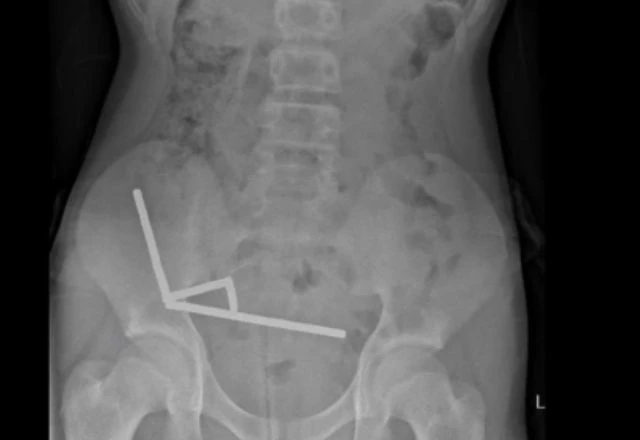

Ele foi internado após quatro dias de dores abdominais e exames de imagem mostraram correntes de ímãs aderidas entre diferentes partes do intestino, unidas pela força magnética. O contato prolongado causou necrose por pressão e risco de perfuração intestinal.

Durante a cirurgia, os médicos encontraram quatro áreas necrosadas e precisaram remover parte do intestino para retirar todos os ímãs. Após oito dias de internação e tratamento de complicações leves, o paciente recebeu alta. O hospital onde o procedimento foi realizado não foi divulgado.